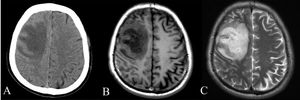

평균 잠복기는 9일(범위 1~21일)이다.[1] 거의 익사한 경우에는 24시간 내에 증상이 나타날 수 있다.[43] 발열, 기침, 근육통 등 감기와 유사한 증상이 나타나며, 폐렴, 패혈증, 농양 등 심각한 증상으로 진행될 수 있다. 간, 비장, 폐, 전립선, 신장 등 다양한 장기에 영향을 미치며, 뇌척수염, 뇌 농양, 급성 신우신염, 패혈성 관절염, 골수염 등 심각한 합병증을 유발할 수 있다.[1]

감염 경과에 따라 다른 심각한 증상이 발생한다. 감염된 사람의 약 1~5%가 뇌척수염 또는 뇌 농양을 앓고, 14~28%는 급성 신우신염, 신장 농양 또는 전립선 농양을 앓고, 0~30%는 목 또는 이하선 농양을 앓고, 10~33%는 간, 비장 또는 장 주위 농양을 앓고, 4~14%는 패혈성 관절염 및 골수염을 앓는다.[1]

흉부 X선 촬영에서는 다양한 결절 병변, 융합되는 결절, 공동 등이 나타날 수 있다. CT 스캔은 간 농양에서 특징적인 "벌집 징후"를 보여주며, 뇌 유비저의 경우 MRI가 CT보다 병변 진단에 더 유용하다.[7]

흉부 X-ray는 다발성 결절 병변이나 융합되는 결절, 공동을 보여줄 수 있다. 혈류 확산이 없는 급성 유비저의 경우, 흉부 X-ray는 상엽 경결 또는 공동을 보여준다.[7] 만성 유비저에서는 폐의 상엽 경결이 서서히 진행되어 결핵과 유사하다.[7] 폐 이외의 간과 비장 농양의 경우, CT 스캔이 초음파 스캔보다 더 민감하다. CT 스캔은 간 농양에서 "벌집 징후"(얇은 중격으로 분리된 격실이 있는 농양)를 보여준다.[7] 뇌를 침범하는 유비저의 경우, MRI가 CT 스캔보다 병변 진단에 더 민감하며, 고리 강화 병변을 보여준다.[7]6. 예방